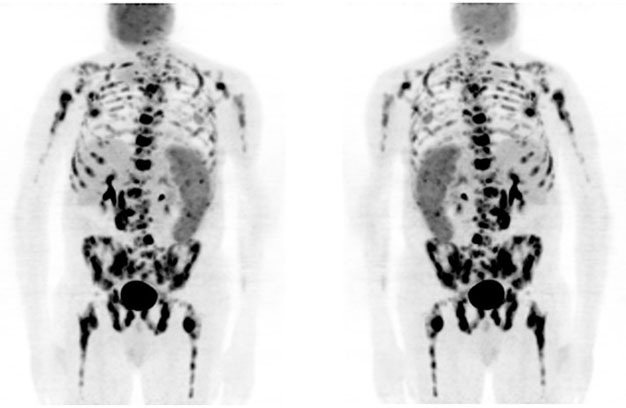

A 65-year-old man with HIV on highly active antiretroviral therapy (HAART) presented with recurrent classical Hodgkin lymphoma (cHL) and visceral crisis. His initial diagnosis was in 2010 when he was treated with 6 cycles of adriamycin, bleomycin, vinblastine, dacarbazine (ABVD) achieving complete remission. The first recurrence was in 2017 when he had extensive lymphadenopathy, splenomegaly, and innumerable osseous lesions. He received 6 cycles of brentuximab, achieving a near-complete remission by April 2018. He subsequently presented in July 2018 with extensive disease relapse, confirmed by excisional lymph node biopsy, and marrow exam documenting 80% replacement of bone marrow by cHL. A PET/CT imaging showed marked progression at multiple sites (Figure 1). At that time, total bilirubin was elevated at 13.3 mg/dL, and alkaline phosphatase of 1142 U/L. His CD4 count was 53 cells/uL. He was treated with nivolumab, receiving only a single dose of 240 mg. However, he was readmitted to the hospital one week later due to significant clinical deterioration, pancytopenia, and progressively worsening liver failure. The total bilirubin escalated to 15.6 mg/dL. He was treated with steroids for possible nivolumab-induced liver injury, and discharged home after a prolonged hospital stay, with hospice care recommended. However, he recovered slowly, without further treatment of HL, and on follow-up after eight weeks he had completely recovered liver function (Table 1). A restaging PET/CT imaging showed a complete response without any evidence of disease (Figure 2). The bone marrow exam was repeated and showed no residual HL. His CD4 count continues to be low at 98 cells/uL, and he is continuing HAART therapy. He is followed closely and the plan is to resume checkpoint inhibitor therapy at disease recurrence.

Figure 1: PET/CT at disease recurrence showing extensive fluorodeoxyglucose (FDG) activity in bone, liver, spleen, and lymph nodes involving hilar, mediastinal, and retroperitoneal regions.